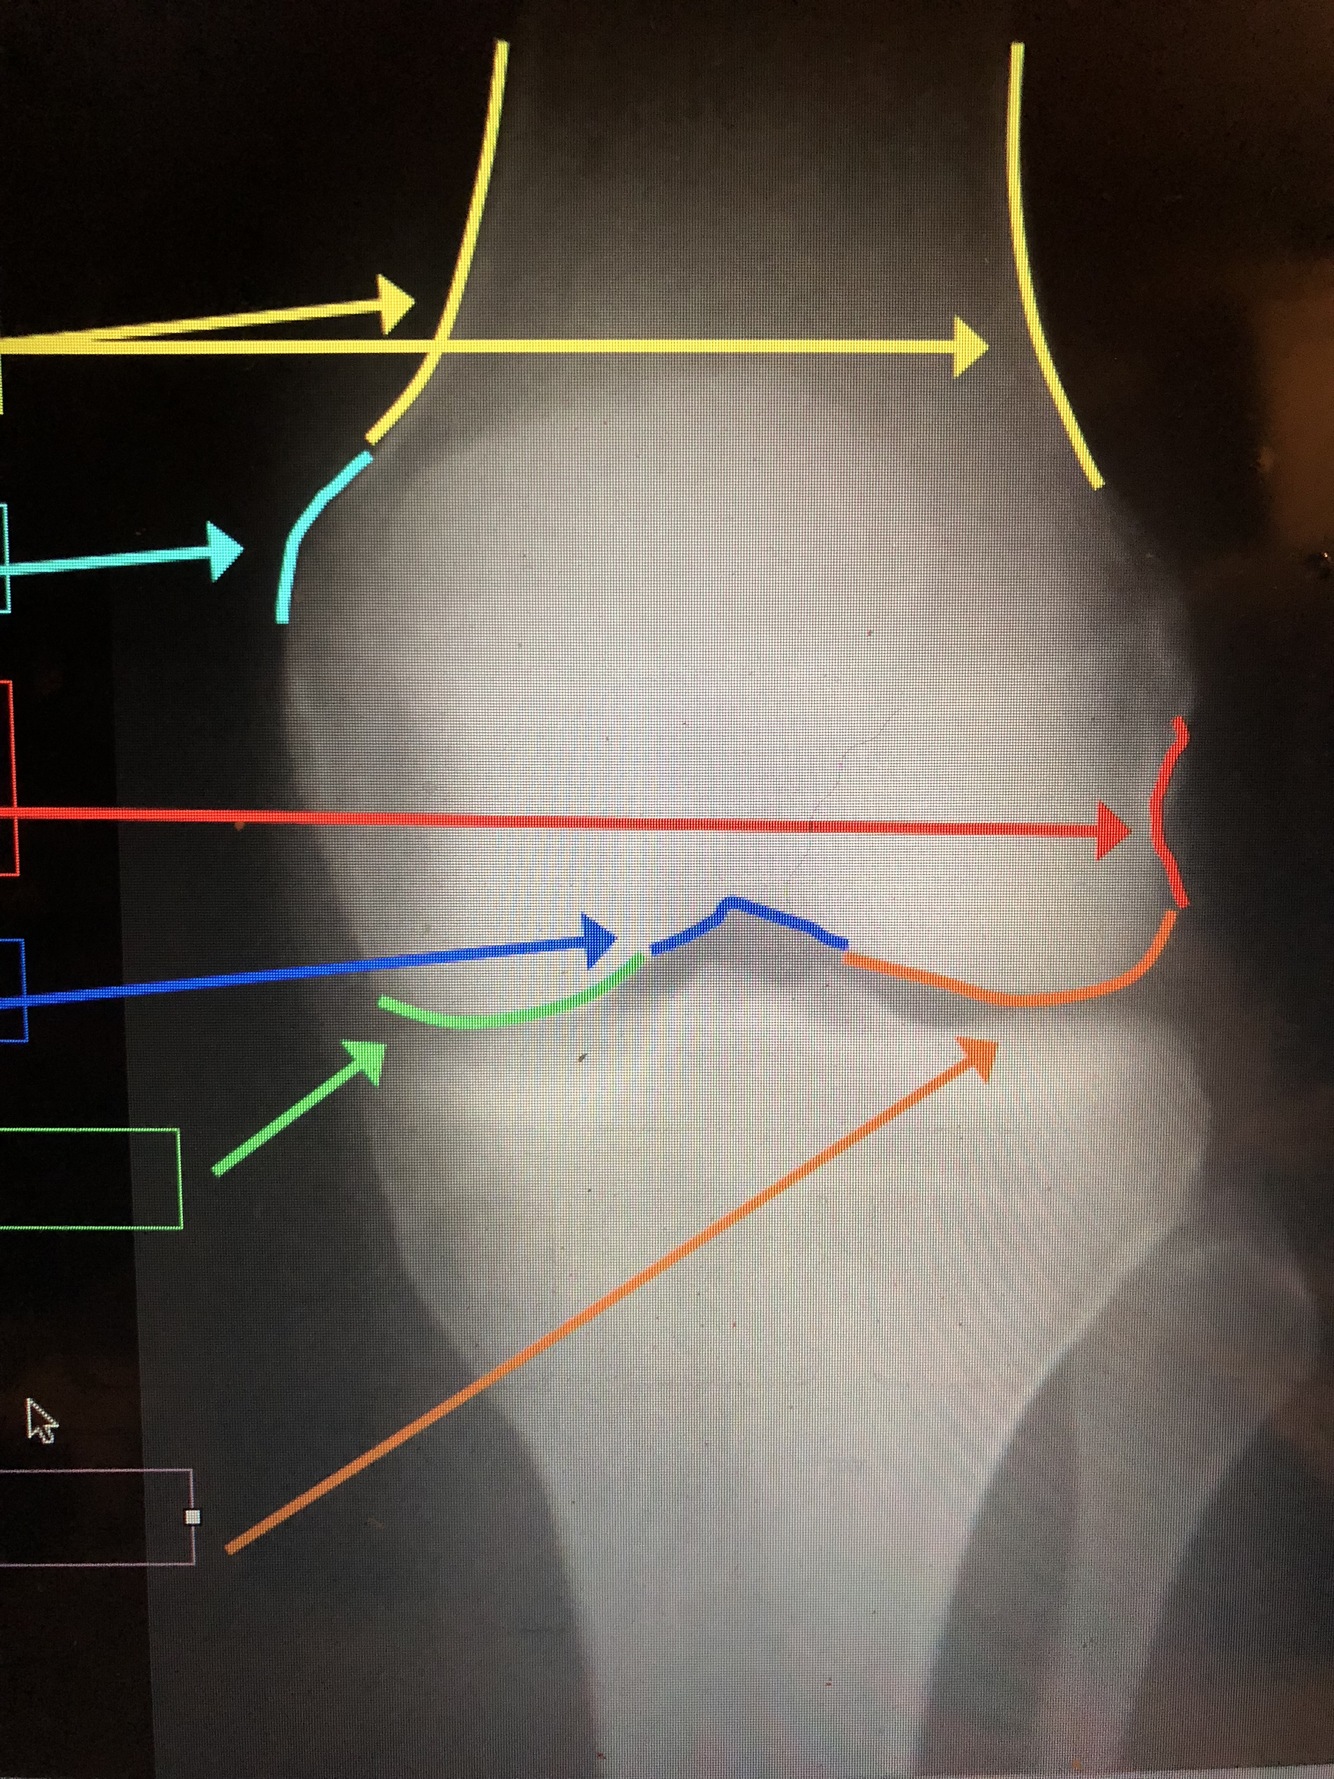

What is the light blue line?

Lateral Femoral Condyle

What is the yellow line?

Medial Femoral Condyle

Cortex – thickest at the diaphysis, but thins out near the metaphysis at the epicondyles

Q

Epicondyles (med. & lat.)

A

What are the yellow lines?

Supracondylar Ridge/Line (med. & lat.)

What is the red line?

Popliteal Groove – where popliteal tendon passes

What is the dark blue line?

Intercondylar Notch

What is the green line?

What is the orange line?